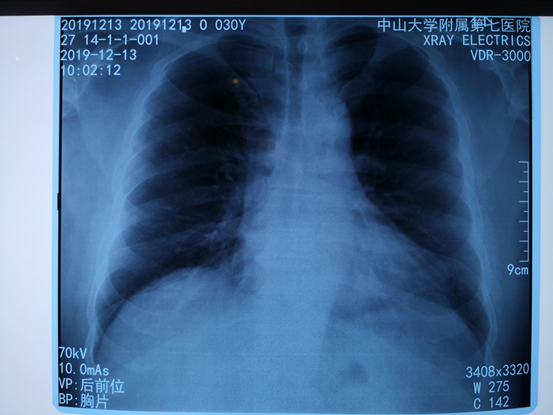

移动医院展开现场,在普外科、泌尿外科和麻醉科团队的配合下,野战手术车上同时进行了两台动物手术,完成了包括脾切除术、部分肝切除术、肠切除肠吻合术、肾裂伤修补术等的实操演练。同时,现场还有医技保障车为手术提供支持和保障,可以即时行X光检查和常规急诊检验项目。

image.png

医技保障车拍出的第一张胸片